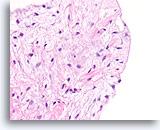

Lobulair carcinoom, Borst FNA, celblok.

Lobulaire carcinoomcellen lijken in het stromaweefsel te zijn ingebed, zodat de indruk wordt gewekt van hypercellulariteit. Dit kan de reden zijn waarom cytologische preparaten van een lobulair carcinoom vaak weinig maligne cellen tonen.

20X

Lobulair carcinoom, Borst FNA, celblok.

Lobulaire carcinoomcellen lijken in het stromaweefsel te zijn ingebed, zodat de indruk wordt gewekt van hypercellulariteit. Dit kan de reden zijn waarom cytologische preparaten van een lobulair carcinoom vaak weinig maligne cellen tonen.

20X